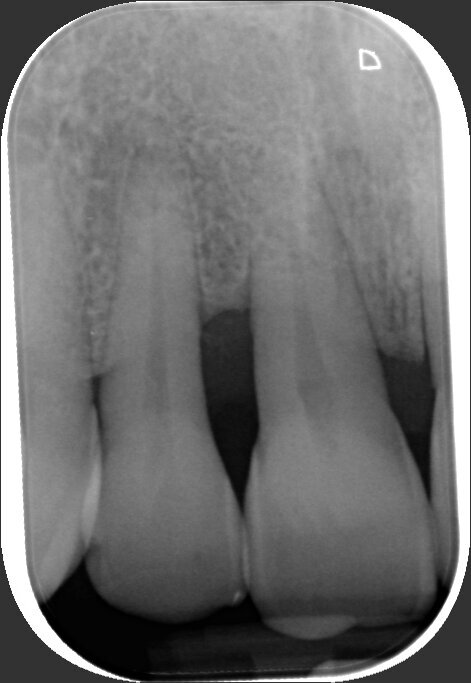

Un paziente di 56 anni non fumatore viene riferito alla nostra osservazione per il trattamento della parodontite. Dopo aver effettuato la diagnosi (parodontite generalizzata Stadio III, Grado C) il paziente è sottoposto a due sedute di scaling sopra gengivale (step 1) e successivamente a 4 sedute di debridement sotto gengivale effettuato con strumenti ultrasonici e manuali (step 2). Al momento della rivalutazione si registra un miglioramento degli indici di placca e di sanguinamento (FMPS e FMBS ≤ 20%) e una riduzione di tutte le tasche parodontali (PD<4 mm) in ciascun sestante a eccezione del secondo sestante. In questa regione si registra una tasca residua con PD = 6 mm a carico dell’elemento 1.1, associata a un riassorbimento osseo radiografico prevalentemente orizzontale (Figg. 1, 2). Considerando il miglioramento di tutti i parametri e degli indici parodontali e la presenza di una tasca con PD = 6 mm a carico di un solo elemento dentario si decide di ritrattare l’elemento 1.1 con terapia non chirurgica (step 3). La nuova ristrumentazione è stata effettuata seguendo il protocollo Clean&Seal che prevede l’associazione di ipoclorito di sodio stabilizzato con amminoacidi e acido ialuronico reticolato ad alto peso molecolare in combinazione con il debridement sotto gengivale. Dopo anestesia locale, è stato applicato all’interno della tasca l’ipoclorito di sodio stabilizzato con amminoacidi e lasciato agire per circa 60 secondi (Fig. 3). Successivamente è stata effettuata la strumentazione sotto gengivale mediante l’utilizzo di strumenti ultrasonici e manuali (Figg. 4, 5). Alla fine della procedura di strumentazione, nella tasca è stata effettuata un’irrigazione con soluzione salina sterile e la procedura di applicazione di ipoclorito di sodio e di strumentazione meccanica è stata ripetuta per 4 volte. Un fattore critico per garantire un risultato migliore è di evitare di instillare qualsiasi soluzione a base di clorexidina nella tasca, in quanto inibisce l’adesione cellulare. Alla fine del trattamento meccanico è stato inserito l’acido ialuronico reticolato ad alto peso molecolare all’interno della tasca per stabilizzare il coagulo e accelerare la guarigione (Fig. 6). Il controllo clinico è stato effettuato dopo 6 settimane dal trattamento con completa chiusura della tasca (Fig. 7).